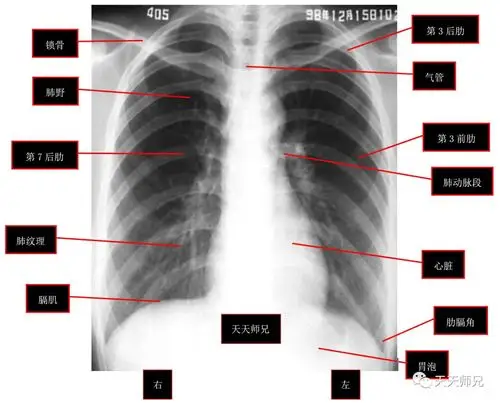

正常胸片及其需要牢记的正常结构:天天师兄说明